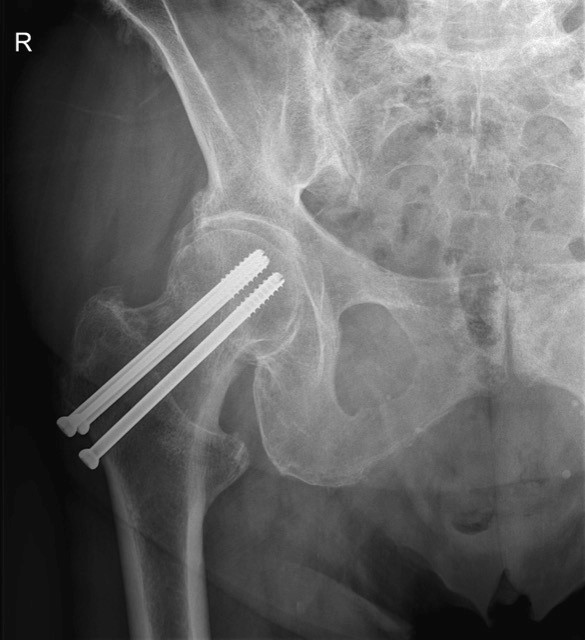

- Gecannuleerde schroeven

- Bij hoge weinig verplaatste heupfracturen vlak onder de heupkop (in het gewrichtskapsel thv de heupnek)

- Jonge patiënten en actieve ouderen met goede botkwaliteit

- Steunverbod gedurende 6 weken